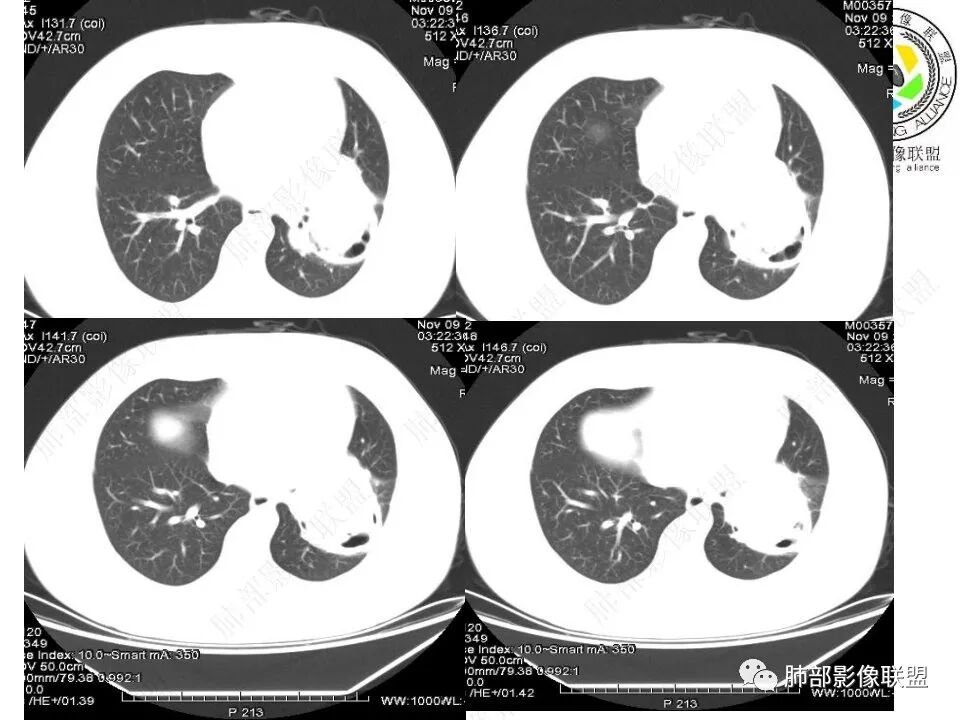

青年男性,体检发现左肺不规则类圆形占位性病变,叶间裂区域,定位胸膜来源。左肺下叶支气管受压狭窄,但管壁光整,未见腔内阻塞或管壁受侵。包块边界清晰,浅分叶,内部密度不均匀,病灶后份见空气新月征。渐进性强化,增强动脉期见分支状血管,蛇纹血管征。肺门纵膈未见增大淋巴结,符合孤立性纤维瘤(SFT)。

3)肺部SFT好发于肺表面如叶间裂等区域,定位相当重要。肿块边界清楚光整,支气管不受侵(或可受压推移)。CT平扫肿瘤多呈等或稍低密度。发生于脑膜的SFT平扫肿瘤多为略高密度病,类似脑膜瘤;肿瘤较小者密度均匀,较大者内部密度常不均匀、见多发灶性或不规则形中心低密度区(细胞稀疏区含有丰富胶原纤维易发生黏液样变性或囊性变),钙化少见。

5)肿瘤的强化程度及方式:增强扫描肿瘤早期实性成分呈不均匀斑片或斑驳样强化,亦可呈“ 地图样” 明显强化,强化程度不一,可呈轻度-显著强化;静脉期持续强化,多期增强及动态增强扫描均呈“快进慢出”型强化,且强化范围逐渐增大并趋均匀。肿瘤内部及周围常见多发粗细不等强化或流空肿瘤血管影。瘤体内“蛇纹血管”在其他诸如硬化性肺细胞瘤、错构瘤等等是非常罕见的。